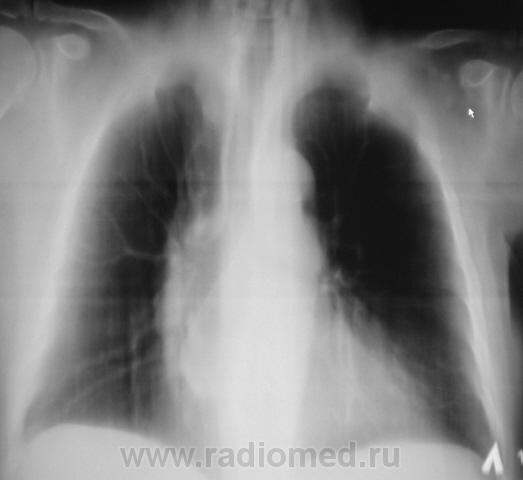

Пациент взят на контроль после флюорографии.

Произведено стандартное дообследование.

Рентгенограмма в прямой стандартной проекции.

похоже в просет "что-то" растет, наверное показана бронхоскопия? А дополнительная тень не ушко правого предсердия?

Хорошие томограмы, жаль нет бочка посмотреть вентиляцию нижней доли, а так конечно в просвете бронха дополнительная тень, предсердие бы оттеснило весь бронх. Надо рекомендовать бронхоскопию.